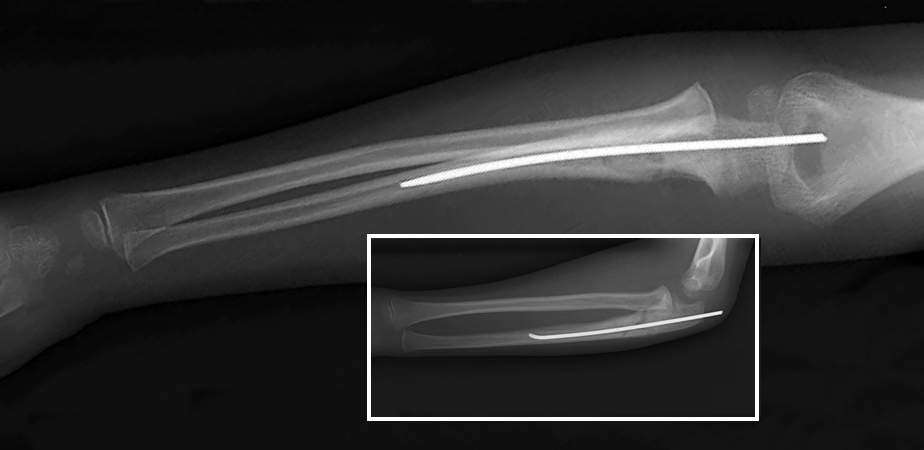

Operative12,16,17

- Surgery is often required when the Monteggia fracture of the ulnar shaft is complete.

- Titanium elastic intramedullary nail fixation is recommended for short, oblique fractures.

- Open reduction and internal fixation (ORIF) with plates and screws is recommended for comminuted or long oblique ulna fractures.17